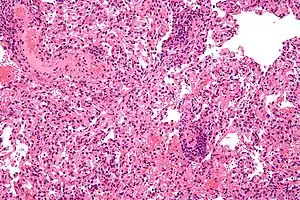

| Micrograph showing lung transplant rejection. Lung biopsy. H&E stain. | |